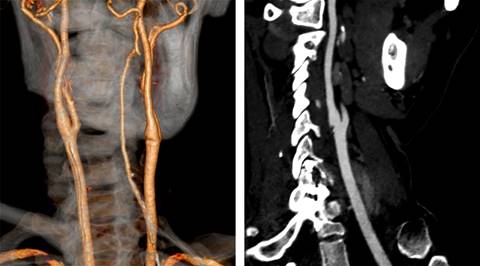

Femenino de 40 años con ataque isquémico transitorio (AIT), en la que se efectuó ultrasonido y angiotomografía que mostraron banda carotídea ipsilateral. La displasia fibromuscular atípica del bulbo o banda carotídea es una patología no ateromatosa implicada en la aparición de infartos cerebrales. La banda carotídea se define como un defecto de llenado lineal en forma de estante en la cara posterior del bulbo de la arteria carótida interna mediante angiotomografía (Figura 1) y/o ultrasonido (Figuras 2 y 3), se reconoce cada vez más como una causa de accidente cerebrovascular criptogénico y/o AIT recurrente, pero la evidencia sigue siendo escasa. Se observa en ambos géneros, con distribución 2:1 a favor del femenino y mayor incidencia en personas de color; cuando son bilaterales (60%) presenta mayor longitud en el lado ipsilateral sintomático que en el contralateral (3-4.5 mm vs 1.85-2.9 mm), observando trombos superpuestos hasta en 30% de los casos con banda carotídea sintomática. A pesar de la recurrencia y gravedad de los accidentes cerebrovasculares originados por embolización asociada con banda carotídea, no existen recomendaciones sobre la mejor estrategia para su manejo; el tratamiento con agentes antiplaquetarios previene la aparición de accidentes cerebrovasculares, pero el tratamiento radical sigue siendo quirúrgico y/o endovascular.

Figura 1: Imagen por tomografía computarizada 3D y fase arterial que revelaron un defecto de llenado focal, lobulado, intimal, en la pared posterior del bulbo carotídeo.